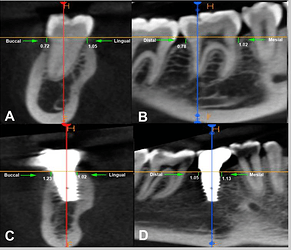

Case photo below provided by: Sharma K, Aggarwal S, Gupta K, Madan R, Tariq S, Narula IS, Gupta S. Three-Dimensional Evaluation of Alveolar Bone Levels Around Dental Implants and Natural Teeth: A Prospective Study.

Evaluation of the marginal bone loss: (A) Buccal and lingual aspect of natural tooth, (B) mesial and distal aspect of natural tooth, (C) buccal and lingual aspect of dental implant, (D) mesial and distal aspect of dental implant.

This study concluded that:

Based on the findings of the present study, it was concluded that the mean marginal bone loss and probing depth( PD) were higher on the implant side than on the natural contralateral tooth during the 18-month follow-up period, and it was the highest on the distal side. Bone loss and PD were higher at the 18-month follow-up than at the six-month follow-up. The duration between the first- and second-stage implant surgery and PD were two significant predictors of bone loss at the mesial and distal sides of the implant. Age and sex were not significantly correlated with bone loss in any of the regions.